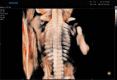

Diagnostic ultrasound (DUS) is, arguably, the most common technique used in obstetrical practice. From A mode, first described by Ian Donald for gynecology in the late 1950s, to B mode in the 1970s, real-time and gray-scale in the early 1980s, Doppler a little later, sophisticated color Doppler in the 1990s and three dimensional/four-dimensional ultrasound in the 2000s, DUS has not ceased to be closely associated with the practice of obstetrics. The latest innovation is the use of artificial intelligence which will, undoubtedly, take an increasing role in all aspects of our lives, including medicine and, specifically, obstetric ultrasound. In addition, in the future, new visualization methods may be developed, training methods expanded, and workflow and ergonomics improved.